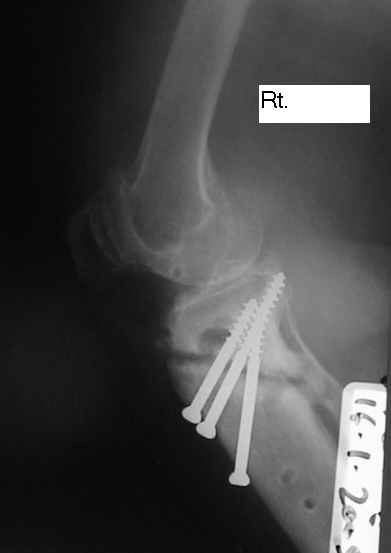

Dorogie Kollegy,Ko mne obratilas' bol'najia, ei 64 goda, ona stradaet ot dvuhstoronnego varusnogo gonoartroza, ei bila vipolnena Visokajia Ostotomjia goleny sprava 01.06.2004, zona osteotomii ne sroslas', plastina bila udalena 12.09.2004 (vidimo iz-za ee nestabilnosti), zona osteotomii tibia bila fixirovana 3-mjia shurupami. Seachas sylno bespokoyat boly v dvuh sustavah, hodit s trudom s pomoshyu Walker, a voobshe ona seachas na invalidnoi kolyaske. Podzkazite, pozhalusta, kak mozno ei pomoch' (snimky prilagayutsa)

Уважаемый Dr.Castro. Мне кажется возможной причиной несращения перелома явилось затекание синовиальной жидкости в зону остеотомии. Проксимальный фрагмент б.берцовой кости мал и "неудобен" для фиксации. Как вариант - можно предложить ЧКДО по Илизарову с временной фиксацией н.з бедра с целью усиления стабильности.Но с аппаратом придется повозиться ( поиграть фрагментами голени).Если нет возможности или желания заниматься аппаратом, придется выполнить СТАБИЛЬНЫЙ остеосинтез мыщелковой или г-образной пластиной, но обязательно с аутопластикой области несращения. Или в виде аутокрошки, или путем перемещения костного трансплантата с дистального фрагмента б.берцовой кости кверху с перекрытием области несращения.

Уважаемый Dr.Castro, я абсолютно согласен с коллегой на счет первого варианта. Использовать пластину с угловой стабильностью не советую поскольку у нас были случаи несращения в этой области при использовании Г-образных пластин после первичного остеосинтеза.В даном случае нужна постоянная и мощная компресия которую можно достичь только методом Илизарова.

U bol'nogo non-union osteotomii tibii. V vozraste 64 let, sdelal bi sleduiezhee:

Work out, proverit', net li infection: ESR, CRP, White cell Scan. Esli infection net togda est' dva varianta:

1. I predpochel bi ego: Total Knee Arthroplasty. Nuzhen budet Revision ( Long stem) tibial Component.

2. Ne sovetuiu delat' geroicheskix postumkov v otnoshenii Non union. Tut est' mnogo problem, ved' esteotomia provedena ne pravili'no s tochki zrenia deformazii. Orientazia ploskosto kollennogo sustava xotia ne ploxa v sagital'noii ploskosti, no vo frontl'noi idet sil;noie otklonenie narozhu i vniz. A nam tida ne nado.